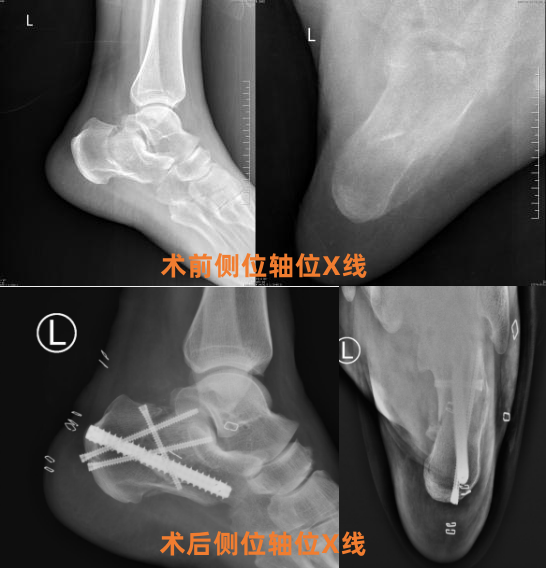

近日,十堰市人民医院创伤骨科1病区成功完成一例采用“跟骨钉中钉内固定系统”的微创手术,为51岁左跟骨粉碎性骨折患者左先生实施精准治疗。术后患者恢复进程显著优于传统术式,次日即下地行走,充分凸显了该技术的临床优势。

患者左先生因不慎从约2米高处坠落,导致左跟骨粉碎性骨折。当在地医院就诊时,医生建议采用传统的大切口钢板内固定手术,但考虑到该术式存在较高皮肤坏死等风险,患者及家属经多方了解后,慕名转至十堰人医创伤骨科1病区寻求治疗。

十堰人医创伤骨科1病区副主任曹洪、主治医师陈驰及其团队接诊后,迅速对患者病情进行精准评估。考虑到患者病情,团队决定采用微创的“跟骨钉中钉内固定系统”为其手术。术中,团队通过专用牵开器和复位器械精准恢复跟骨长度、高度及宽度,有效避免内外翻畸形,并利用交锁钉结构实现骨折稳固支撑。

曹洪主任介绍,跟骨骨折手术方式较多,以往多采用传统L型入路切开复位内固定术,但该术式易引发切口感染、皮肤坏死等并发症。相比之下,“钉中钉”技术具有显著优势:一是微创操作,软组织损伤小、出血少,并发症风险低;二是术前待术时间短,术后渗出少,可缩短住院周期;三是生物力学稳定性强,允许早期康复训练,符合加速康复外科(ERAS)理念。目前,该技术已在该院多例跟骨骨折患者中成功应用,临床效果显著。